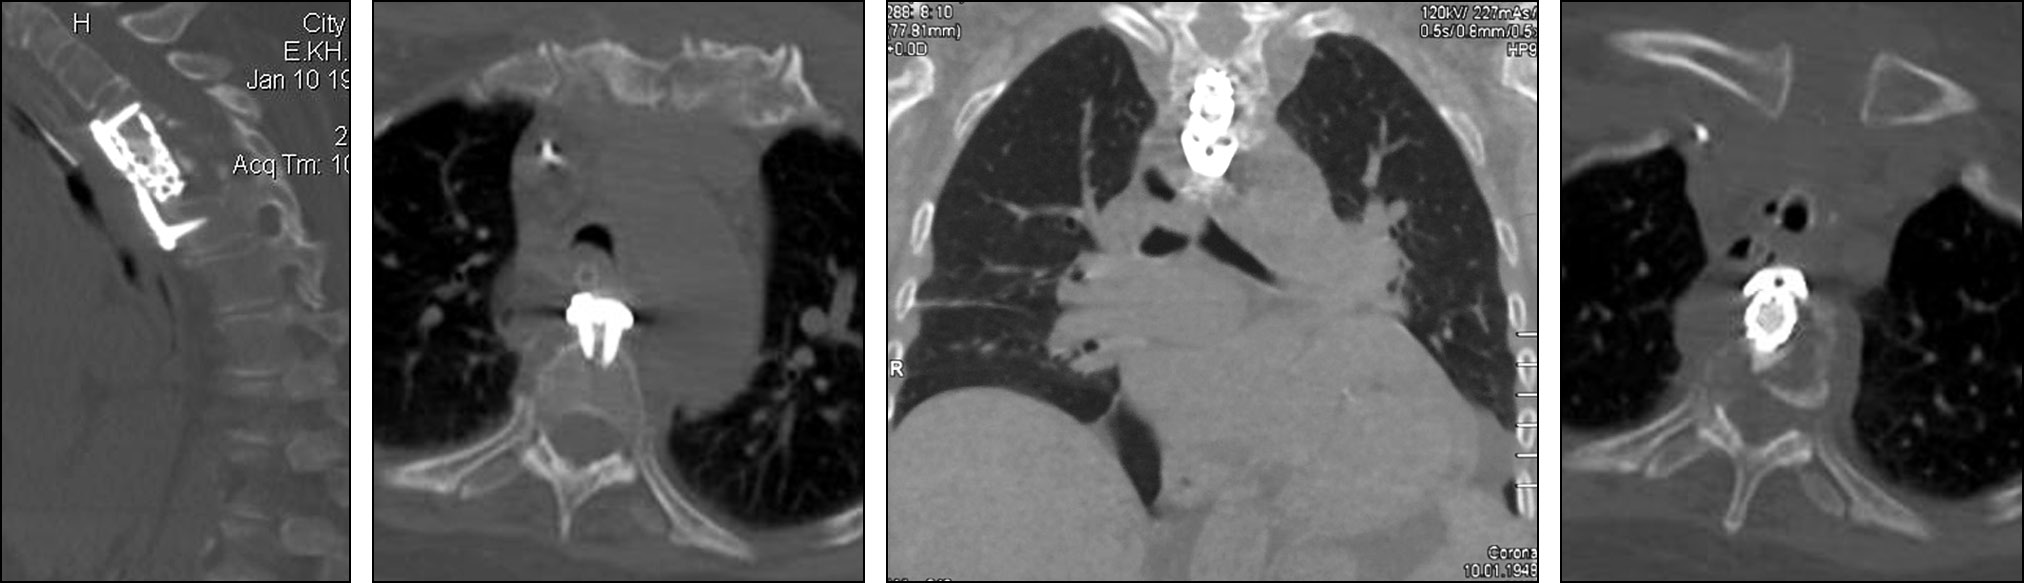

На послеоперационных КТ выявлен регресс кифотической деформации грудного отдела, компрессия спинного мозга устранена (рис. 10). В клинической картине наблюдалось частичное восстановление силы в нижних конечностях.

Рис. 10. Послеоперационные компьютерные томограммы грудного отдела позвоночника. Положение имплантируемых металлоконструкций удовлетворительное, кифотическая деформация и компрессия спинного мозга устранены.

Fig. 10. Postoperative CT scans of the thoracic spine. The position of the implanted metal structures was adequate, kyphotic deformity and spinal cord compression were eliminated.